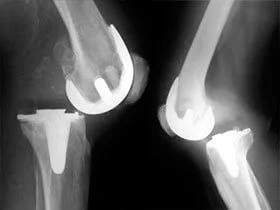

Вывих эндопротеза

Т.к. искусственный сустав не является полноценной заменой суставу настоящему, то его функциональные возможности, соответственно, ниже. При некоторых неосторожных движениях в суставе может произойти вывих эндопротеза. Как и при вывихах в натуральных суставах, считается, что вывихивается дистальный компонент протеза по отношению к проксимальному (например, в тазобедренном эндопротезе вывихивается головка эндопротеза).

При произошедшем вывихе, его вправляют под наркозом. После этого ногу иммобилизируют. По окончании острого периода всегда сохраняется риск повторных вывихов. Если закрытым путём не удаётся вправить вывих, делают операцию открытого вправления вывиха.

Перелом эндопротеза

Может ломаться ножка либо шейка эндопротеза. Это обусловлено т.н. "усталостью" металла, развивающейся вследствие постоянных нагрузок на металлоконструкцию.

Даже протезы из самых прочных сплавов не застрахованы от подобных осложнений.